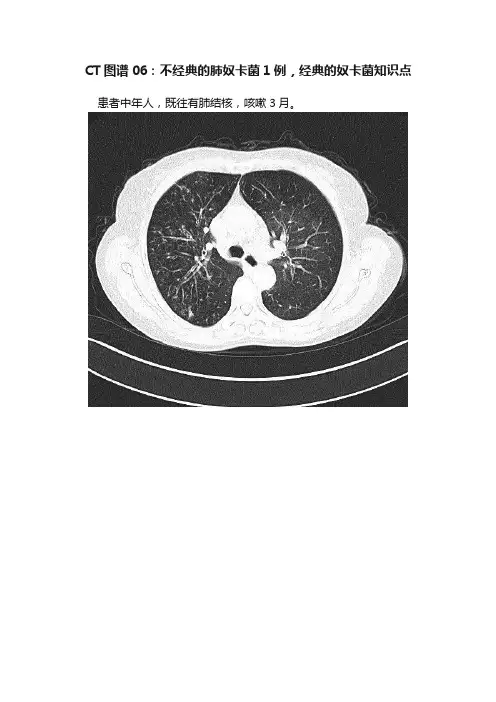

CT图谱06:不经典的肺奴卡菌1例,经典的奴卡菌知识点患者中年人,既往有肺结核,咳嗽3月。

诊断?支扩并感染!做个支气管镜!刷片抗酸阳性,什么病?结果,刷片是弱抗酸染色+!痰培养:豚鼠耳炎诺卡菌!诺卡菌,就是奴卡菌!奴卡菌,属于放线菌家族!奴卡菌属放线菌目,是G+、需氧的丝状细菌。